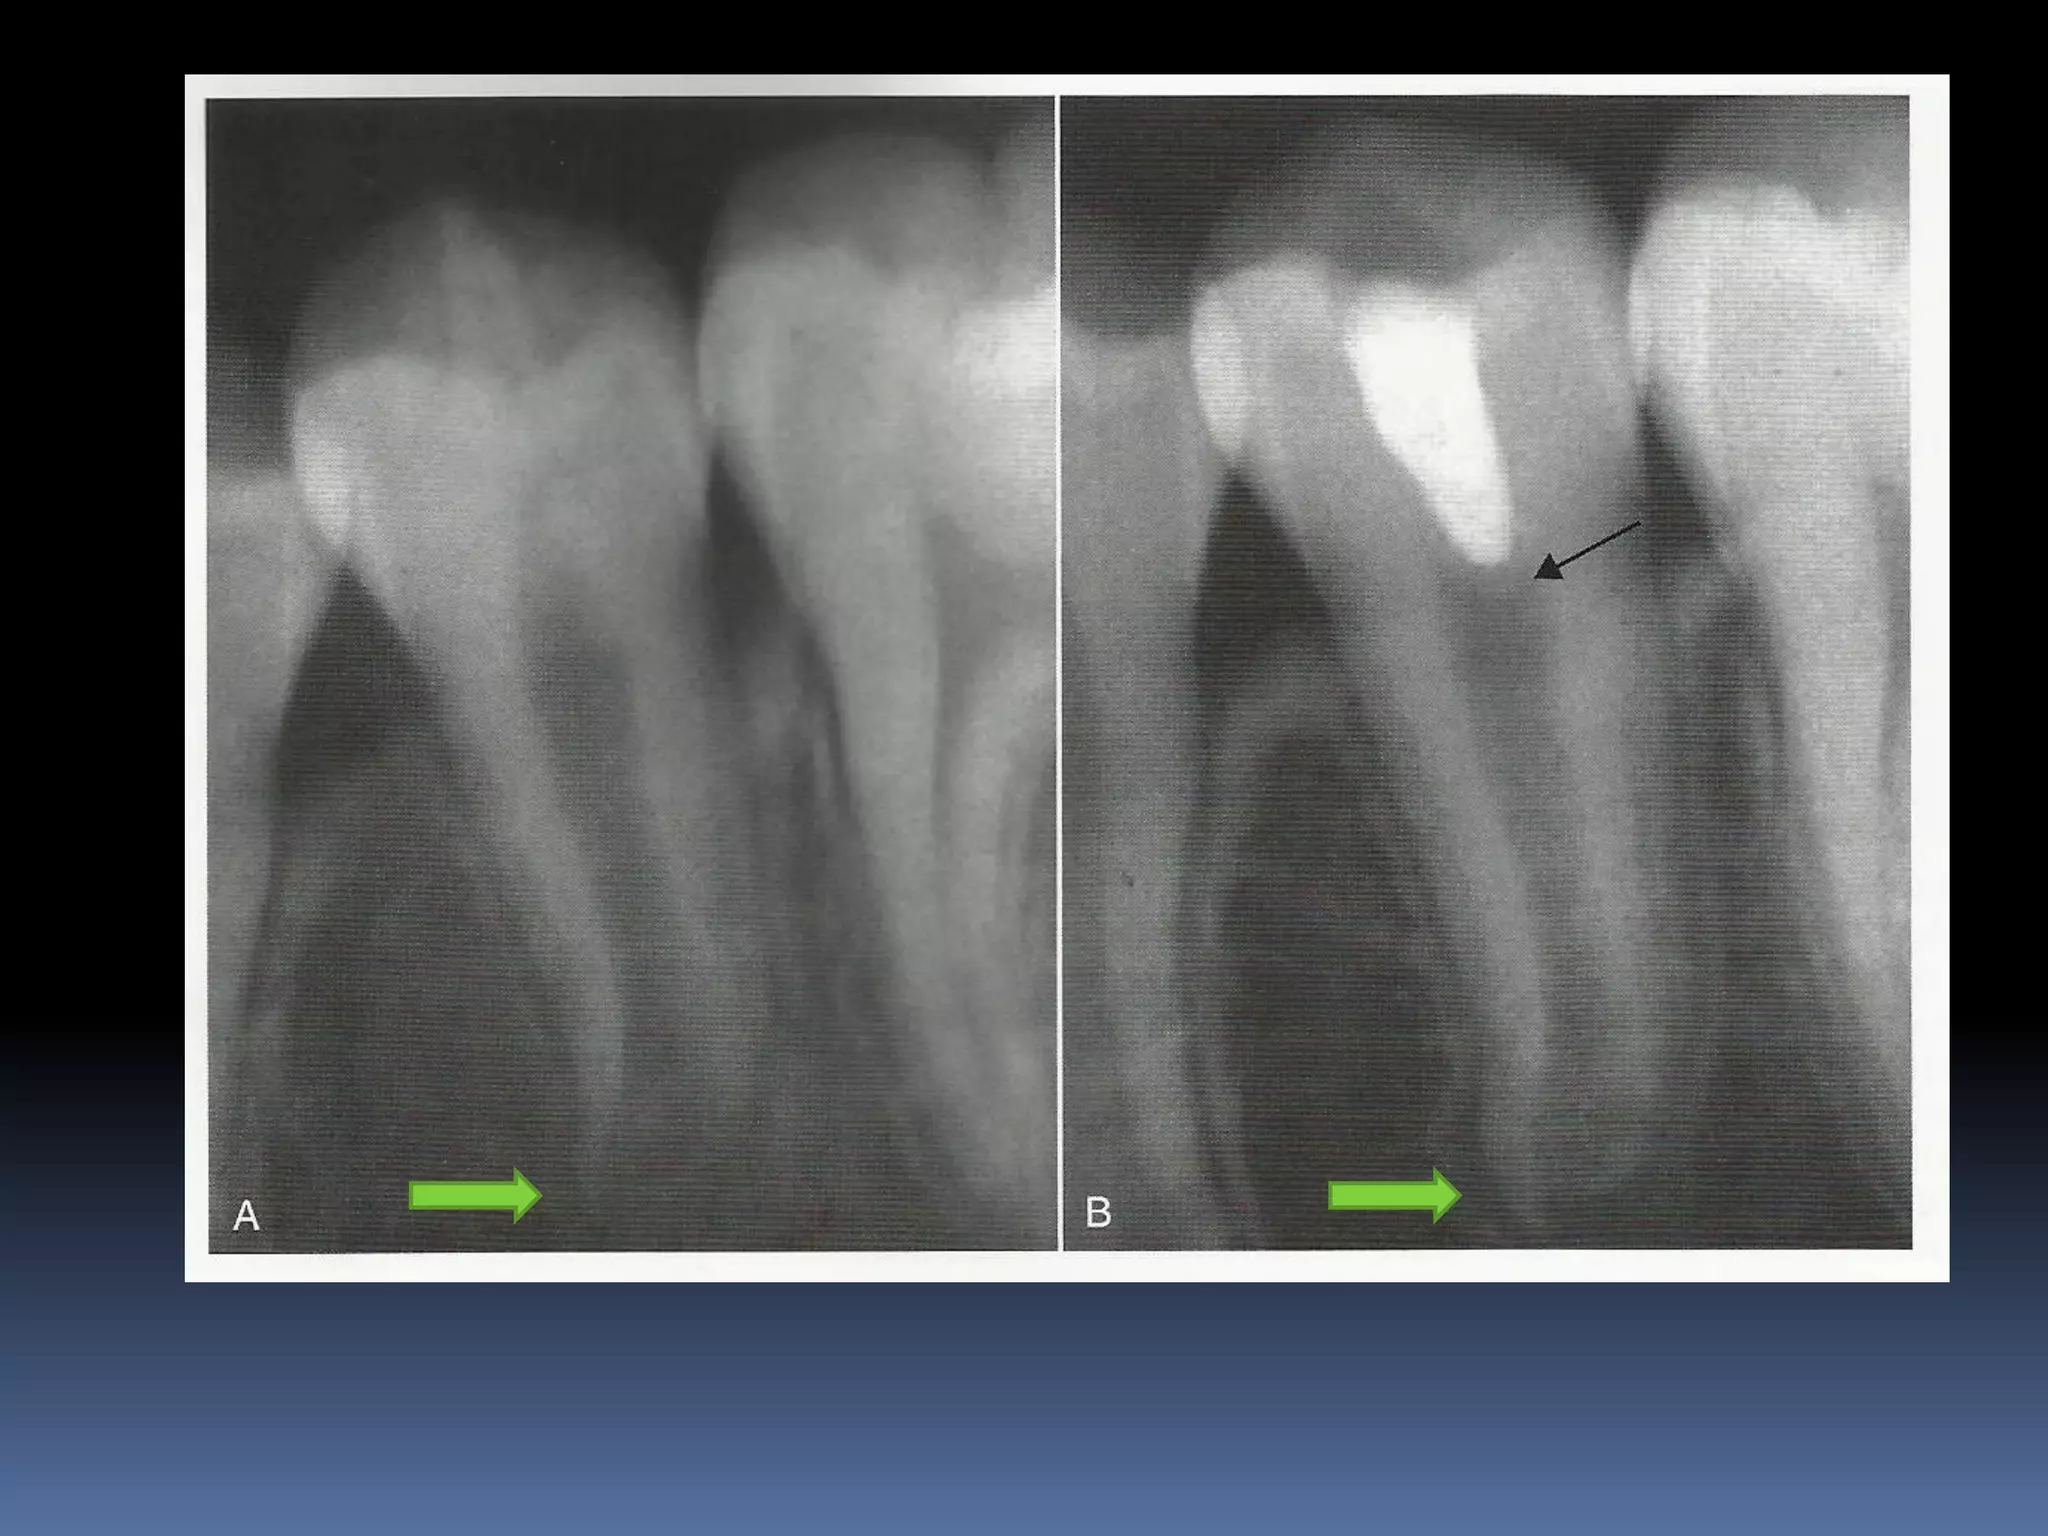

Diagnosis and assessment: History  Subjective symptoms  Diagnostic tests  Radio graphs A radiolucent area usually surrounds the apex of an immature root with a healthy pulp

APEXOGENESIS A Vital Pulp Therapyprocedure performed to encourage continued physiologic development and formation of the root end. Since the main objective is to maintain the vitality of the radicular pulp the pulp must be vital and capable of repair

Trauma / mechanicalexposure / Caries  Small exposure - Pulp capping  Large exposures - Cvek pulpotomy Pulpotomy

Technique: 1. Anesthesia andrubber dam isolation 2. The inflamed pulp tissue is removed using a sharp round bur in a high speed hand piece with water coolant for superficial 2-3mm of pulp amputaion [Cvek pulpotomy] 3. Or removal of the entire pulp to the level of the canal orifices using a large Spoon excavator 4. Hemorrhage is controlled by pressure on a cotton pellet moistened with saline. [ failure to achieve hemorrhage indicates pulpal inflammation]

The exposed pulpis rinsed with 2.5% sodium hypochlorite MTA or hard set calcium hydroxide is placed over the amputated pulp. MTA is prepared by mixing MTA powder with saline in the ratio of 3:1 on a glass slab. The mixture is placed on the exposed pulp and patted with a moist cotton pellet. MTA sets in the presence of moisture. Wet cotton pellet is placed over MTA and the tooth is restored.

The patient isthen put on a periodic recall for 1-2yrs at every 6 month interval. Commonly encountered • Calcific metamorphosis • Internal resorption In such cases NSRCT initiated.